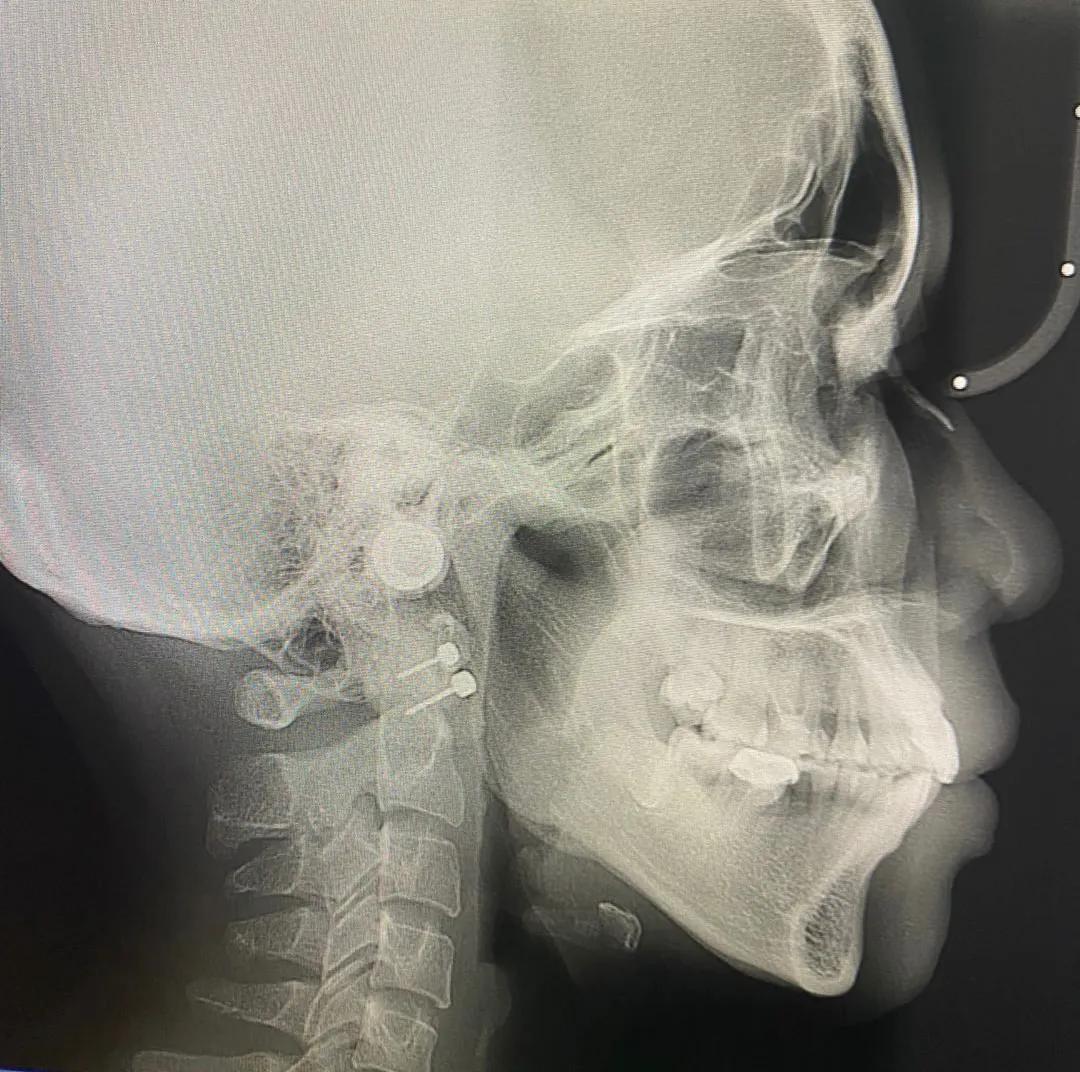

我在2020年下半年我补过的蛀牙因为上火隐隐作痛,然后我去了深圳市宝安人民医院做了检查拍了一次牙片,医生看了我牙片说左上颚蛀牙治疗不彻底,现在依然在发炎,右边下颚拔大牙后没有补上,缺牙过久导致受力不均,旁边的牙齿前倾牙列变形,可以通过矫正把牙齿排放整齐减少牙周病,隐形牙套矫正五万,钢牙不适用与我。

我经过一个月的预约排号预约到了香港大学深圳医院的矫正医生,我去看诊的女医生说了矫正的后遗症副作用后我还是坚持矫正,她说她要离职把我推荐给别的医生还问我喜欢怎么样的医生,然后我说我喜欢专业和态度好的医生。然后转给了一个男医生,他的治疗方案与我的想法不谋而合,我决定在港大医院做。因为我打耳洞对耳钉过敏,所以我要试着带一个月。